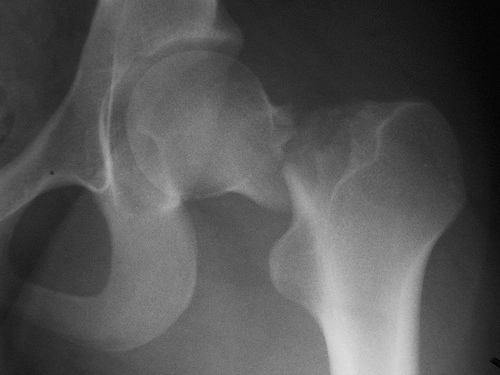

El Odanacatib pertenece a una nueva clase farmacológica de inhibidores de la catepsina K, una enzima activa en la resorción ósea. Los estudios de fase III mostraron sin embargo un aumento de eventos adversos cerebrovasculares.

Un estudio halló que más del 75% de los pacientes fracturados recibían fármacos que aumentan el riesgo de fractura. Además, la mayoría los siguió utilizando después. JAMA Internal Medicine, 22 de agosto de 2016

Es importante prevenir la osteoporosis luego de la cirugía BMJ, 27 de julio de 2016

Aunque el intervalo ideal entre densitometrías no está establecido, la estabilidad o aumento de la DMO entre estudios se asocia a un mejor pronóstico. Annals of Internal Medicine, 19 de julio de 2016